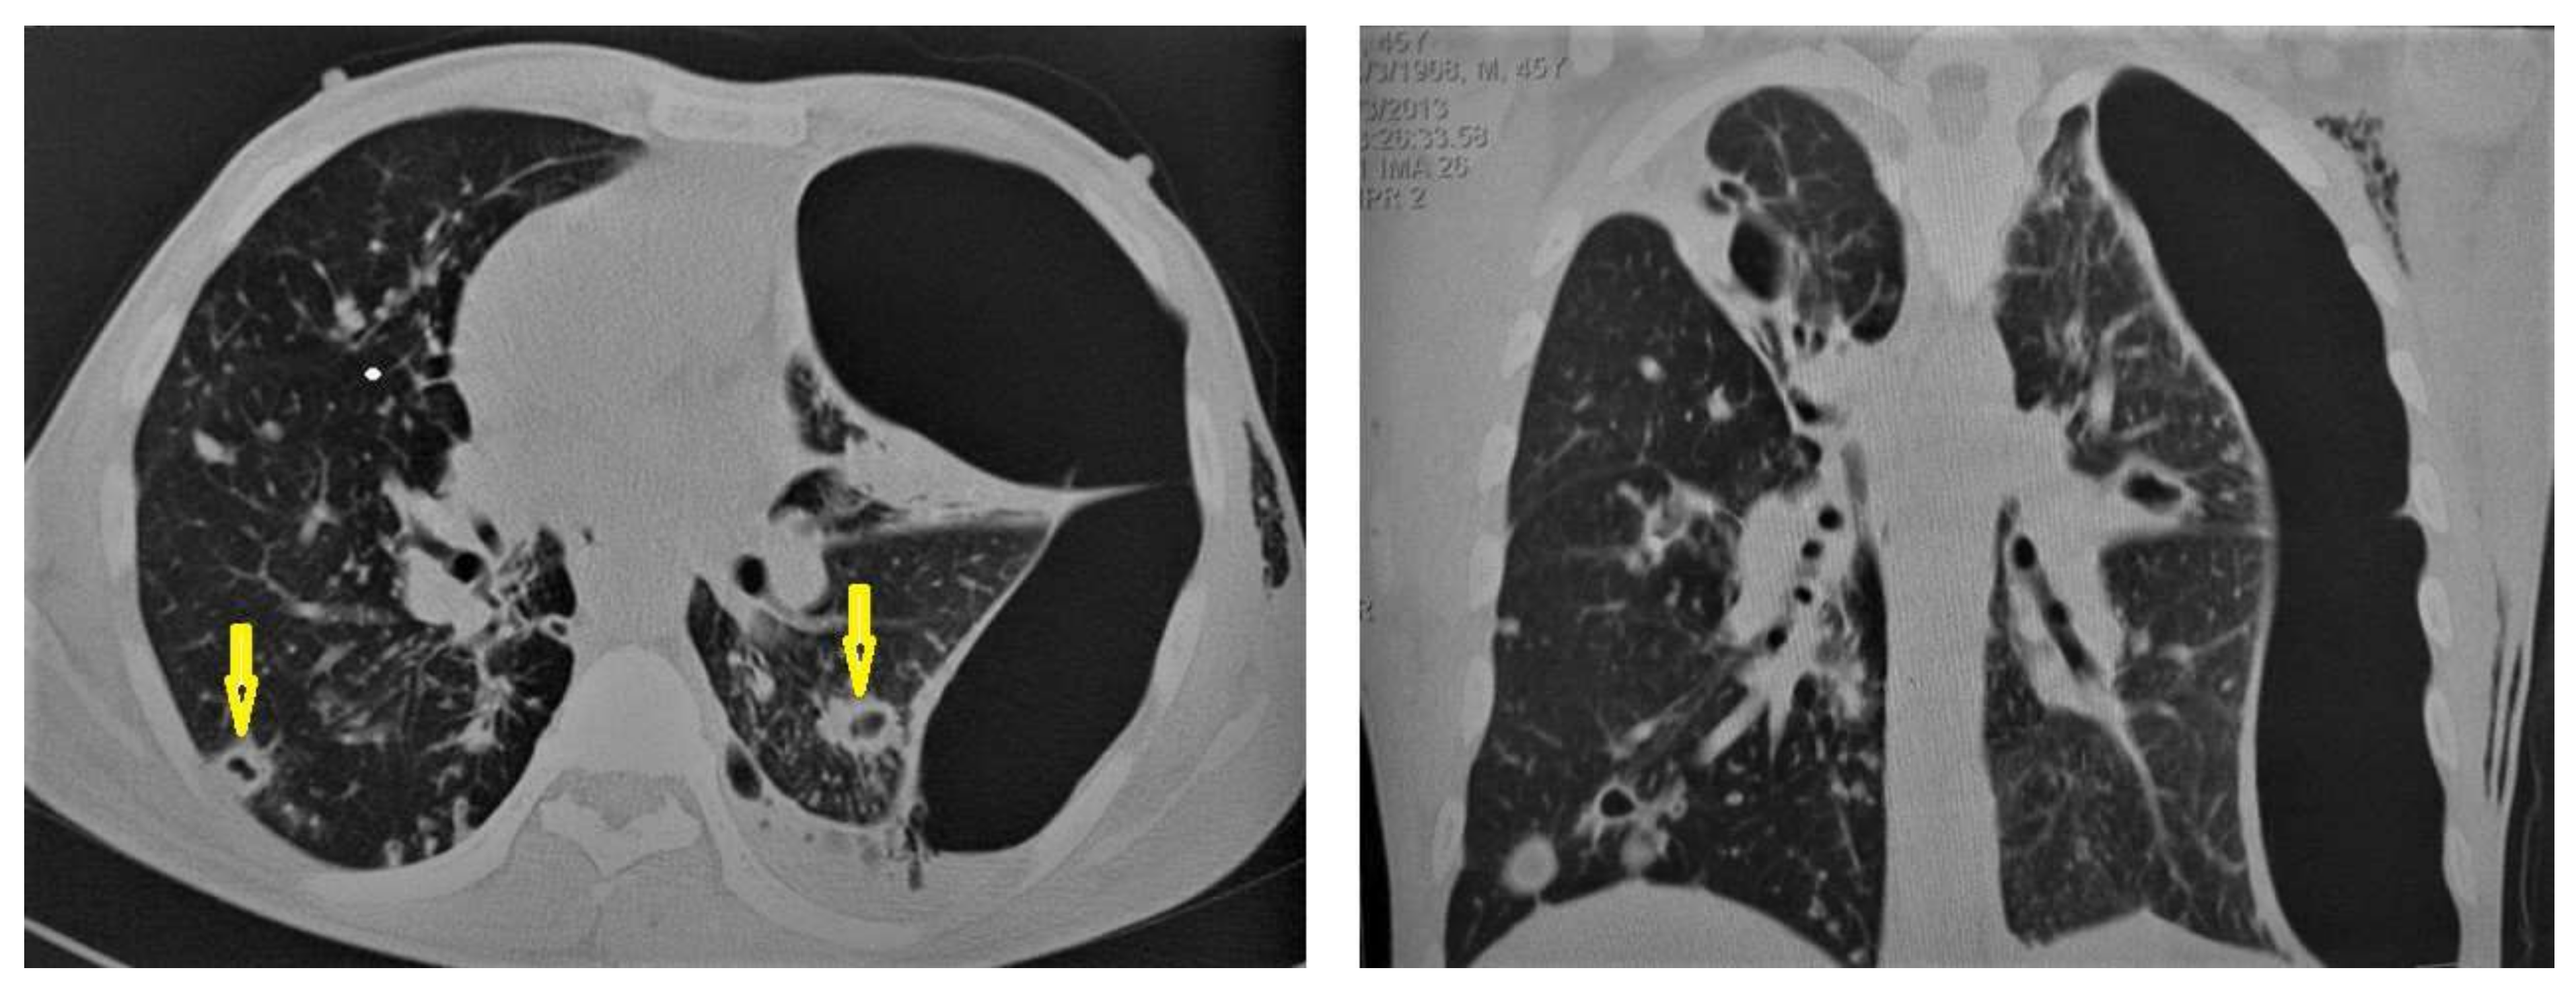

• Cavitation (Figure 3 and Figure 4) is a common finding in postprimary TB, and it is characterized as being several centimeters in size with thick irregular walls. Cavities are often seen within consolidation and may persist after treatment predisposing to a bacterial or fungal superinfection or adjacent vascular erosion causing hemoptysis [1,10]. In postprimary TB, both consolidation and cavitation have a predilection for the apical and posterior segments of the upper lobes and the upper segments of the lower lobes [1,14]. This predilection of TB is attributed to the relative over-ventilation, high oxygen tension, and delayed lymphatic clearance in these regions [16]. Thick wall cavities are an important differential diagnosis of a pulmonary abscess, septic emboli, aspergilloma, granulomatosis with polyangitis (Wegener’s granulomatosis), lung malignancy, and others [17].

• Centrilobular nodules (Figure 4 and Figure 5) occur due to the communication of active TB with the bronchial tree resulting in endobronchial spread. It occurs in most cases of active TB. It appears as centrilobular nodules and a tree-in-bud sign on CT images [1,10]. The tree-in-bud pattern is seen on high-resolution CT images as 2–4 mm centrilobular nodules of soft tissue density that are connected to multiple branching linear structures of the similar caliber, arising from a single stalk. It commonly occurs in the endobronchial spread of TB and is highly suggestive of active TB. However, a tree-in-bud is a CT manifestation of the diverse entities of lung diseases, including TB, cytomegalovirus, respiratory syncytial virus, obliterative bronchiolitis, diffuse panbronchiolitis, cystic fibrosis, airway-invasive aspergillosis, allergic bronchopulmonary aspergillosis, and pulmonary metastasis [18].

Figure 4. Reactivated TB in a 34-year-old women. (a) Chest radiograph shows extensive reticular shadowing and multiple cavitary lesions in both lungs. (b) Coronal reconstruction CT shows multiple cavitary lesions (c) in both lungs, the large two in the posterior segment of the upper lobe, and in the apical segment of the lower lobe of the left lung. (c,d) Axial CT images of the lung show multiple cavitary lesion, the largest in the posterior segment of the left upper lobe, with multiple centrilobular (long arrows) and tree-in-bud (short arrows) appearance.